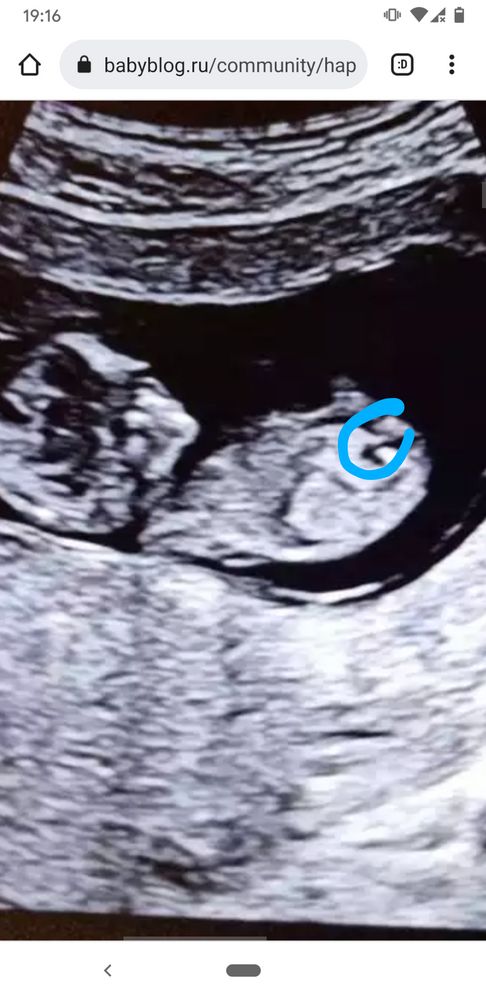

Полина Анисимова, у вас малыш немного развёрнут, поэтому видно плохо. Предполагаю, что вот тут, но могу ошибаться. Изображение

Полина Анисимова, а я думаю, что вот бугорок, в кружочке) Изображение

Юлия Sonnце, я тоже сейчас гуглила, ваш бугорок похож на бугорок))